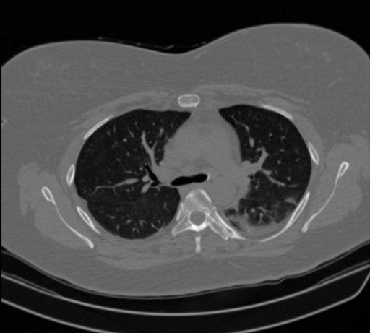

Figure 1 shows four CT scan slices, two from a non-COVID-19 CT scan, on the left and two from a COVID-19 scan, on the right. Bilateral ground glass regions are seen especially in lower lung lobes in the COVID-19 slices.